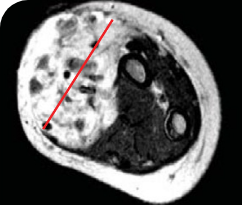

Reduction in tumor burden1

MRIa imagery of the brain. Red line indicates the maximum dimension.1

aMRI, magnetic resonance imaging.

Response to VITRAKVI1

- Patient achieved a confirmed partial response after 4 cycles of VITRAKVI with a 45% reduction in tumor burden

- Following 6 cycles of VITRAKVI, the patient was referred for definitive limb-sparing surgery

- Pathology revealed a complete pathologic response and clear resection margins with scar tissue noted

Pre- and post-treatment imaging, by DuBois SG et al, is licensed under CC BY 4.0.